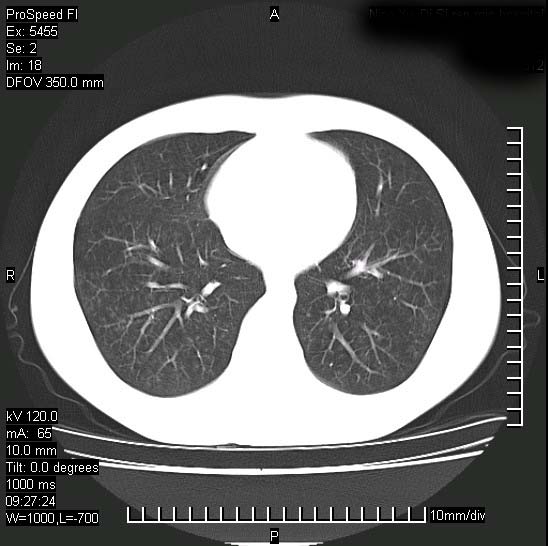

以下是引用zjzjr在2008-12-3 20:50:00的发言:[br]考虑泛细支气管肺炎,建议进一步检查除外肺出血性疾病如含铁血黄素沉着症、肺肾综合征等。

以下是引用zjzjr在2008-12-3 20:50:00的发言:[br]考虑泛细支气管肺炎,建议进一步检查除外肺出血性疾病如含铁血黄素沉着症、肺肾综合征等。

以下是引用光线在2008-12-3 20:19:00的发言:[br]双肺间质性改变。